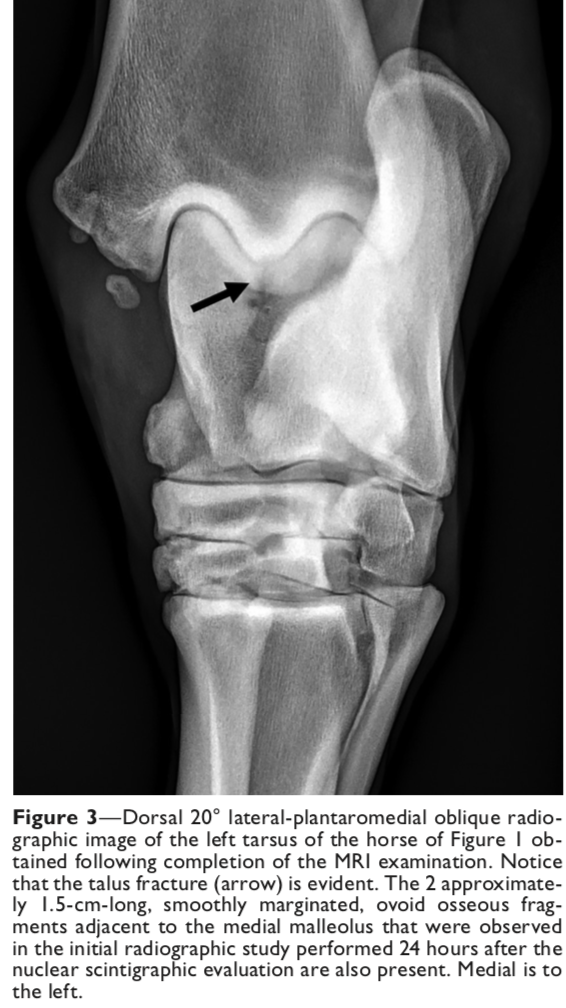

Most appropriate radiographic view for incomplete sagittal fractures of the talus

D 10-20° L- PMO